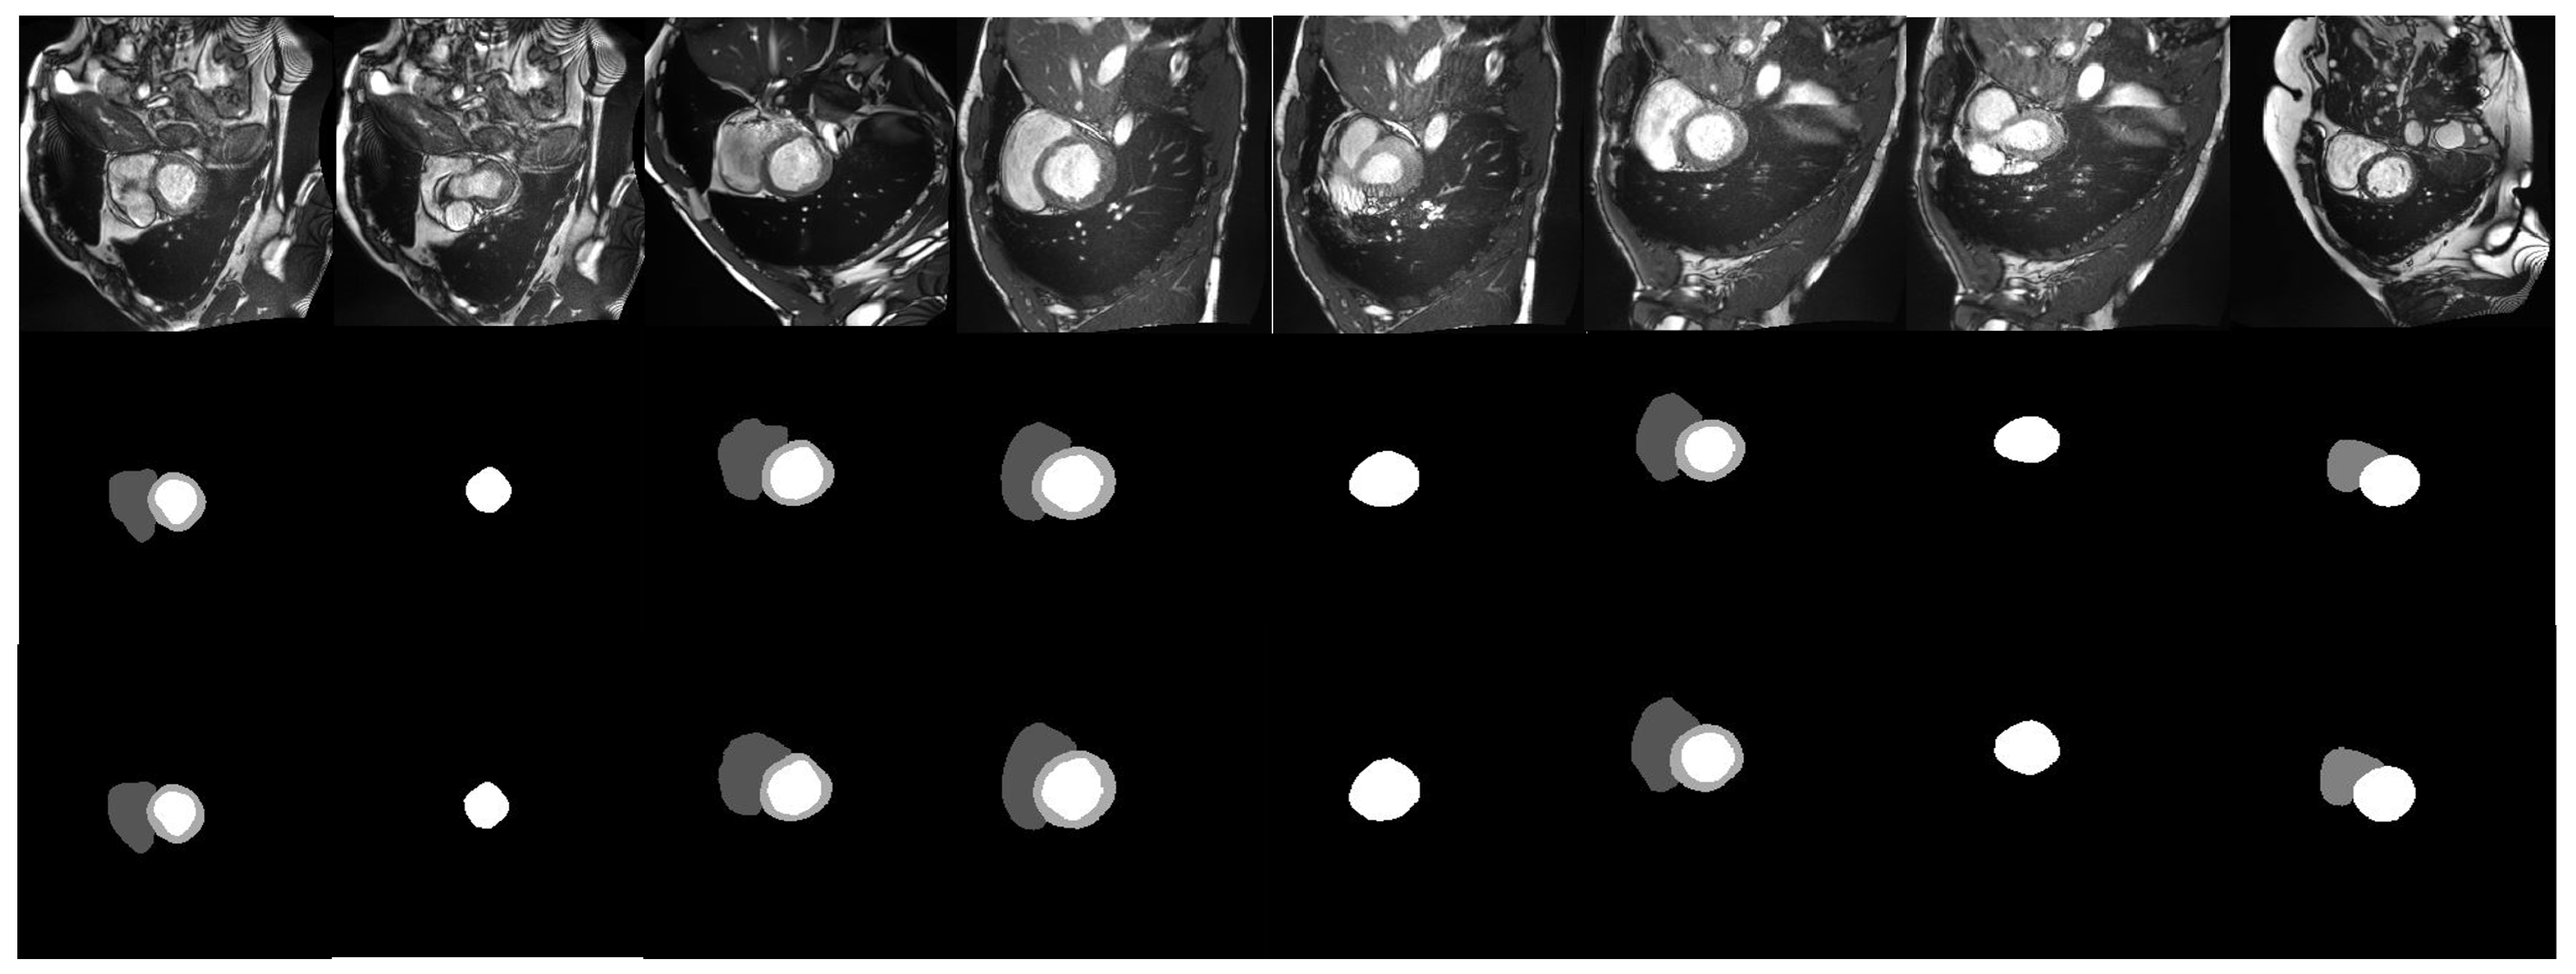

Eight testing cases are chosen to show the qualitative evaluation of nn-TransUNet on the ACDC dataset. A visualization of the 8 cases is shown in Figure 5. The first row is the raw images, the second row is the corresponding prediction generated by nn-TransUNet, and the third row is the ground truth images for the test case. As shown in Figure 5, the shape and volume of the predicted images match well with the ground truth images, which indicates that the performance of nn-TransUNet is good.

Figure 5.

Visualization of 8 testing cases.